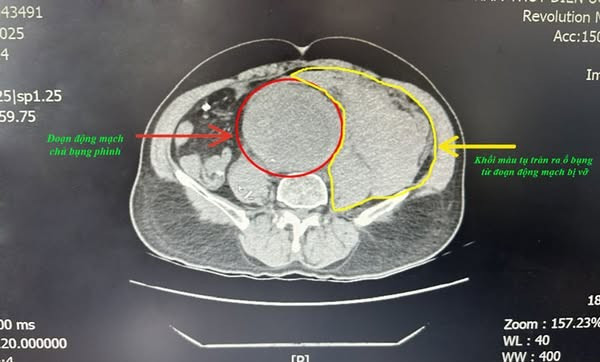

Kết quả chụp CT.Scanner phát hiện phình động mạch chủ ngực đoạn dưới thận lan đến động mạch chậu 2 bên, khối phình đã vỡ gây tụ máu sau phúc mạc số lượng lớn.

Khối phình vỡ máu tràn ra ổ bụng trên phim chụp - Ảnh BVCC